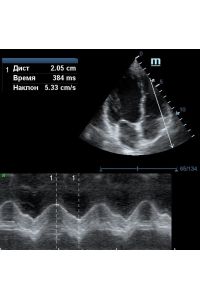

TAPSE - показатель амплитуды движения латеральной части кольца трикуспидального клапана, позволяет количественно и быстро оценить систолическую функцию правого желудочка, норма которого составляет более 17 мм. Главным условием является проведение линии М-режима параллельно стенке правого желудочка в апикальном четырех камерном сечении, что легко достигается при Free Xros.